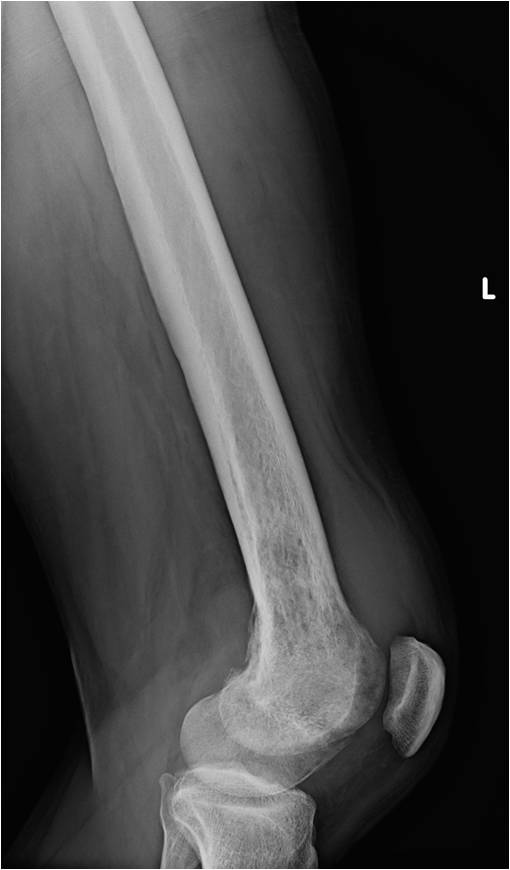

On radiographs, most MFHs of Bone are located in the metaphysis and present as purely osteolytic permeative lesions without a periosteal reaction and without mineralization (Fig. 1 &2). On MR images, MFH of Bone has ill-defined margins usually with cortical destruction of bone and extension into the soft tissues. It is usually hypo- or isointense to muscle on T1-weighted images (Fig. 3) and heterogeneous high intensity on T2-weighted images (Fig. 4-6).

Fig. 2

Fig. 1 & 2: Plain x-rays of an MFH of the distal femur. AP (Fig. 1) and Lateral (Fig. 2) view shows a permeative lytic lesion in the distal femur without a periosteal reaction and without mineralization. The lesion is poorly circumscribed.